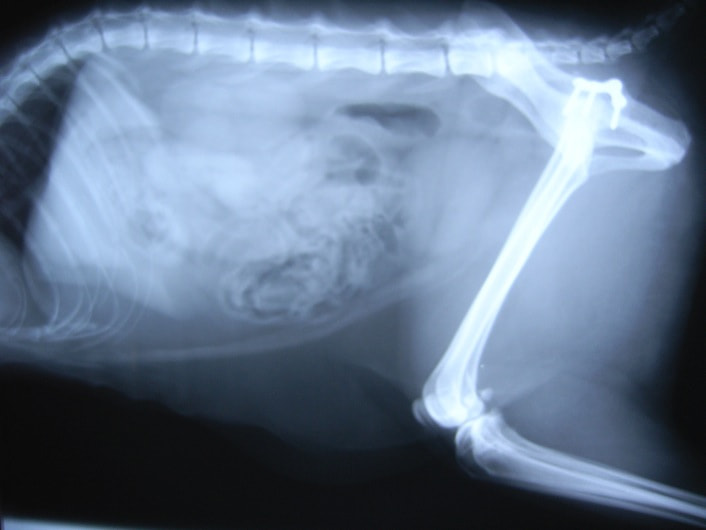

症例:交通事故による椎体脱臼

柴犬:9歳、避妊雌

交通事故直後、胸腰部に激しい疼痛、両後肢に完全麻痺を認め、シェフシェリントン徴候を呈していました。レントゲン検査において、第11-12胸椎間の脱臼が認められました。

脊髄の減圧、脊柱管の再構築・安定化を目的に、片側椎弓切除術およびMatrixMANDIBLE Plateによる椎体固定を実施しました。

隣接椎体を架橋するようにプレートを設置しました。

術後レントゲン写真